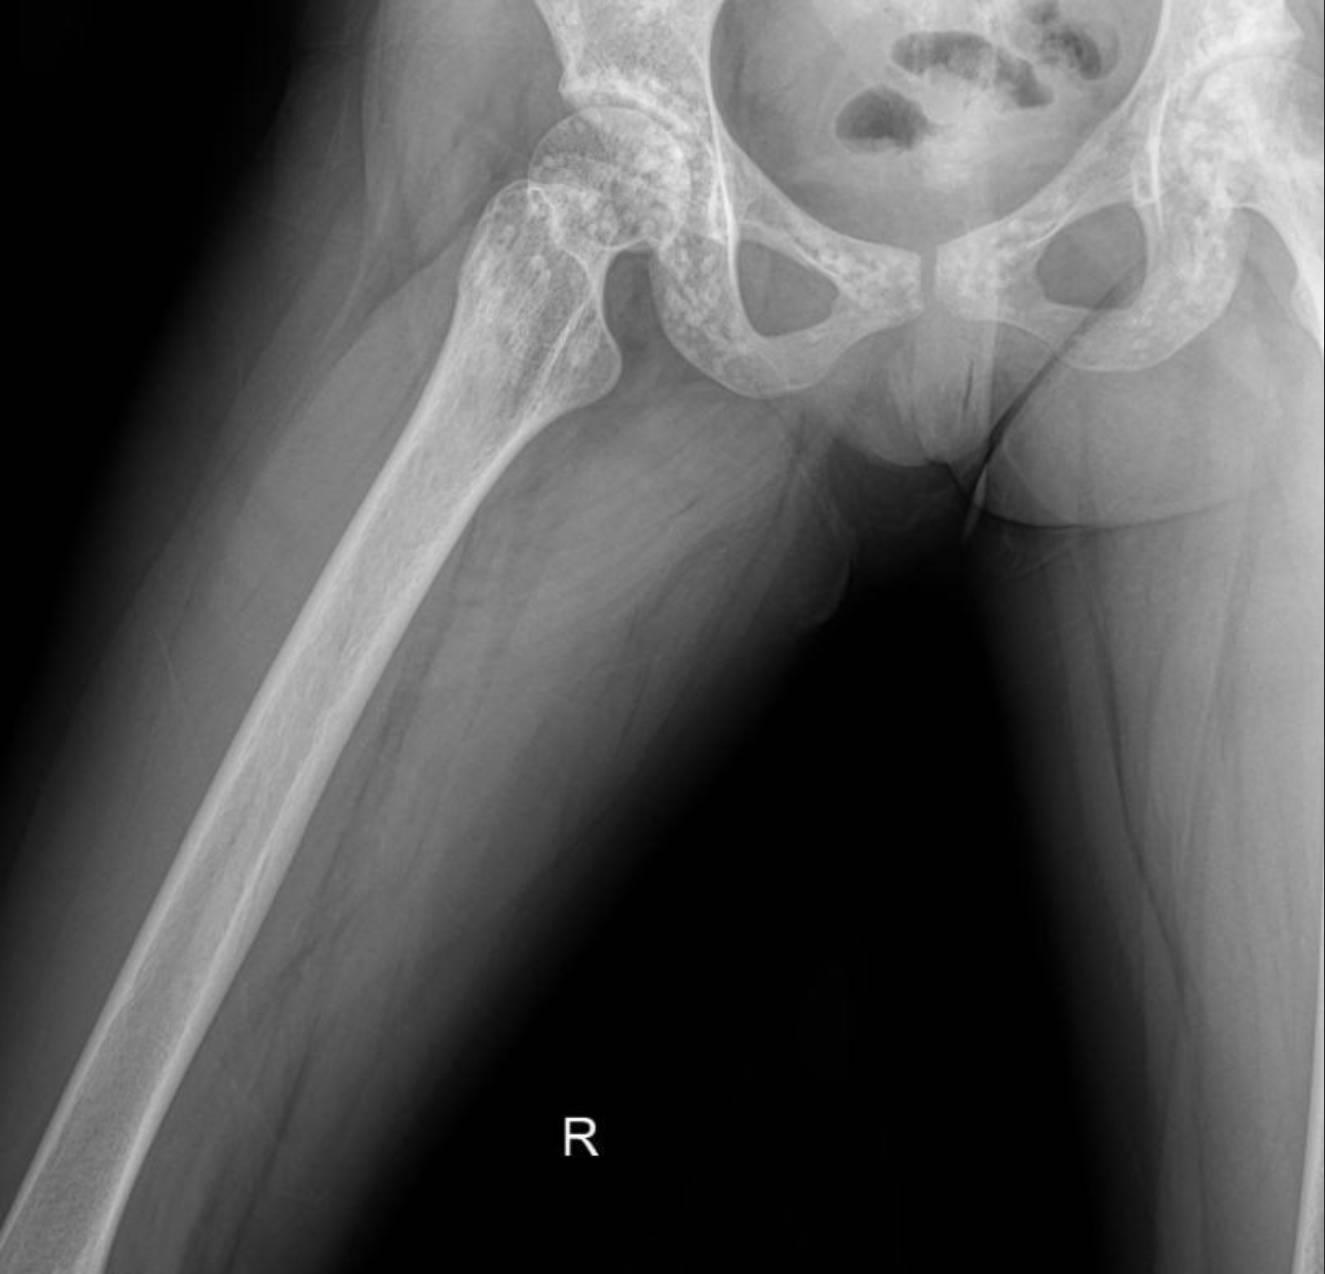

The X-rays of the pelvis, knees, elbows, wrists, and ankles demonstrate multiple, discrete, well-circumscribed sclerotic (densely opaque) lesions distributed symmetrically throughout the bones. These lesions are typically ovoid or spherical, varying in size, and are predominantly located in the epiphyses and metaphyses of long bones, as well as in the carpal and tarsal bones and the pelvic girdle.

Specifically:

- Pelvis and Hips: Numerous small, dense, rounded opacities are scattered throughout the iliac bones, sacrum, ischium, pubic rami, and around the femoral heads and greater trochanters.

These widespread, symmetrically distributed sclerotic bone islands are pathognomonic for hereditary osteopoikilosis (also known as osteopathia condensans disseminata). This condition is typically benign and often discovered incidentally. While not directly related to her renal artery stenosis or hypertension, its discovery is crucial for patient management as it can sometimes be associated with other connective tissue disorders, though often it is an isolated finding.